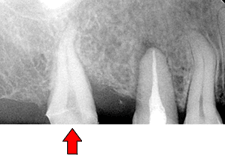

症例.6 傾いた歯をまっすぐ起こす

|

|

|

| 赤矢印の方向に咬む力が加わると 白矢印部分の骨が吸収していきます。 |

装置を入れました。 比較的小さな装置です。 |

|

|

|

|

| 矯正により正しい方向に力を加えられるようになりました。 | ||